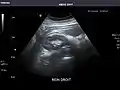

Right kidney

Kidneys: Right and left kidneys measure 11.5 cm and 12 cm in length respectively. No hydronephrosis. Small left lower pole kidney cyst.